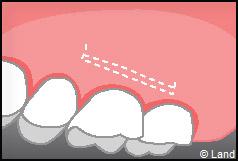

LES TECHNIQUES SANS APPORT DE GENCIVE :

Elles font appel à des lambeaux de gencive restante à proximité des récessions, qui sont déplacés et repositionnés sur la récession.

Dans ce cas le lambeau est déplacé latéralement pour combler la récession.